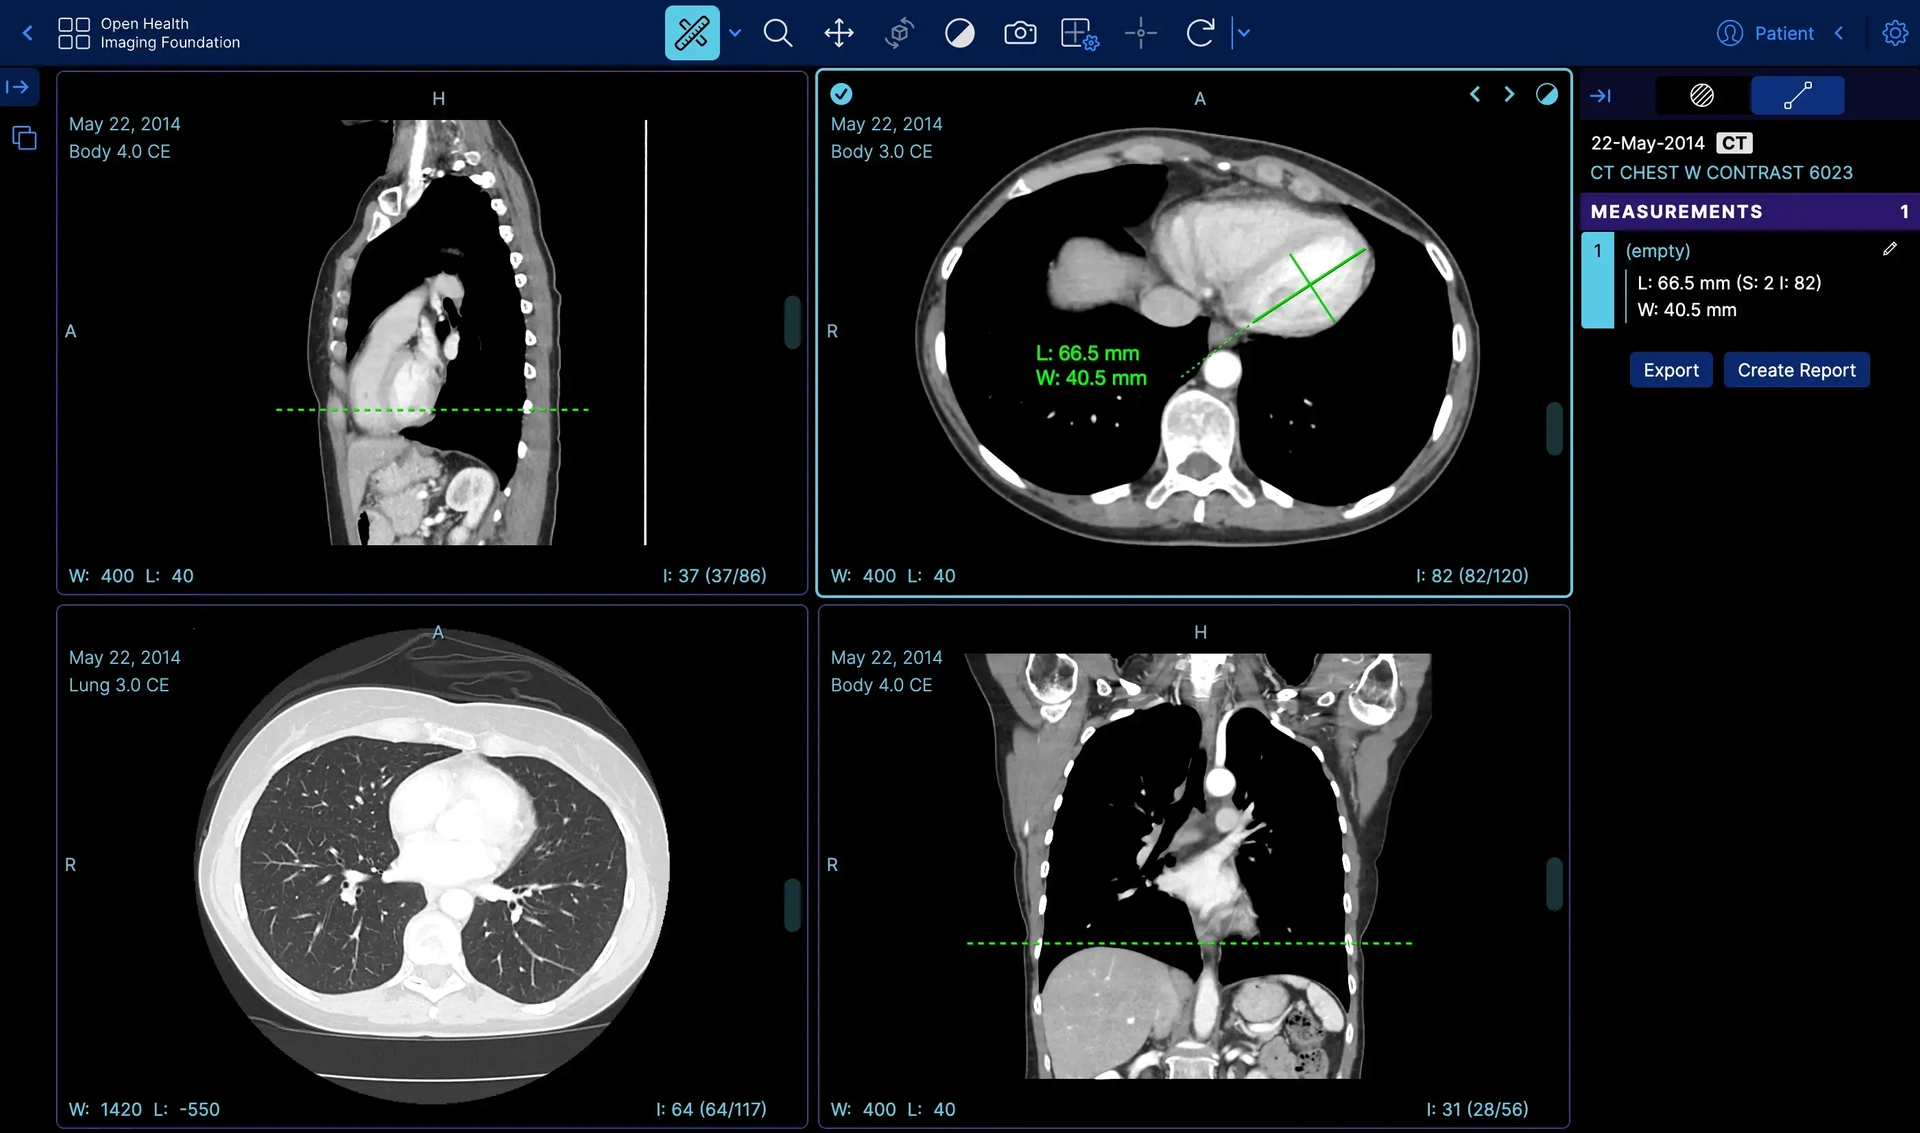

ระบบ PACS บนเว็บแบบครบวงจร Pure Web-Based รองรับ DICOM มาตรฐาน ใช้งานได้บนทุกอุปกรณ์และทุกเบราว์เซอร์

แพลตฟอร์ม PACS หลัก จัดเก็บและสื่อสารภาพ DICOM สำหรับโรงพยาบาลทุกขนาด รองรับ On-Premises และ Cloud

Web Viewer รองรับ MPR, Window/Level, Annotation ออกแบบตาม Workflow ของคุณ